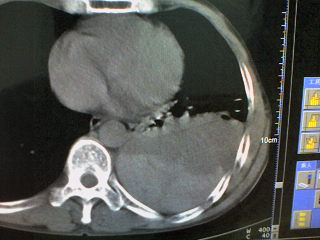

患者,男 51岁。突发性胸痛来诊。

起病急,症状重,应先除外心脏及大血管病变,左侧胸腔内可见囊实性病变,胸壁可见引流管影,建议提供完整的图像资料及相关的临床资料。

病变是胸腔内的。前部液体引出来的是血红色的液体。现在鉴别其后缘的高密度是什么?

这是一例胸膜外血肿形成的病例啊。。后面的高密度为凝血块。

手术证实的。